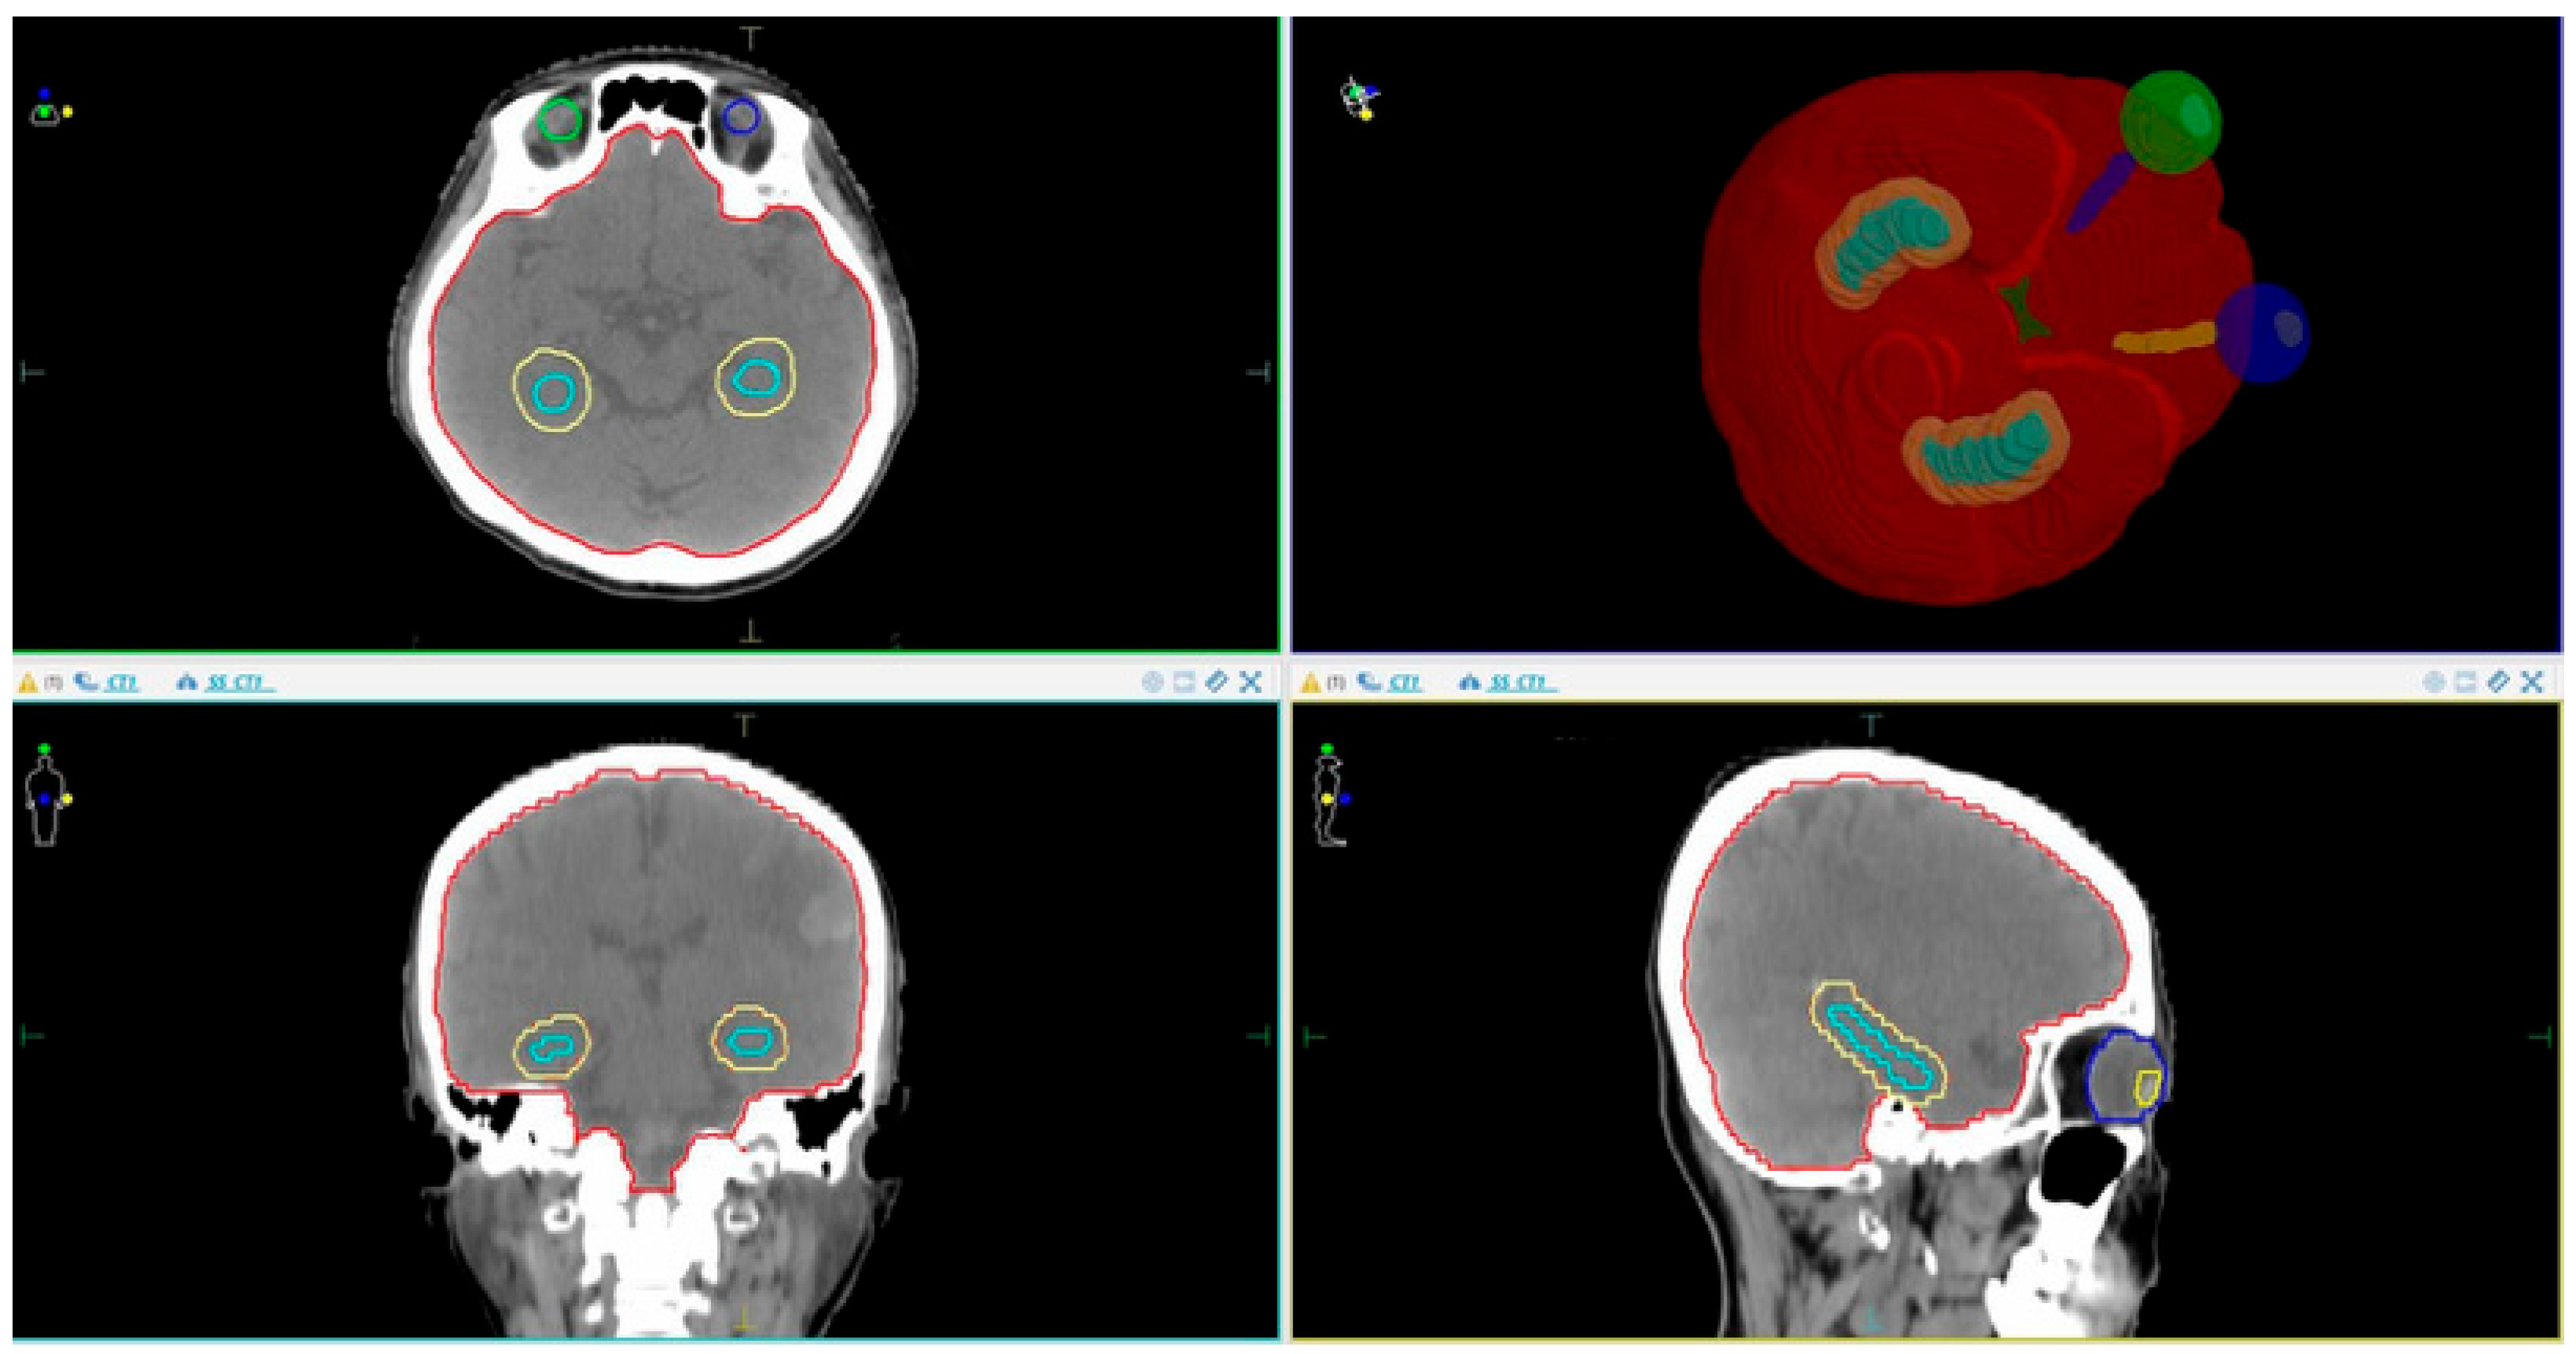

2.3.1. Patient Simulation CT Imaging and Volume Delineation Data

- CTV (Clinical Target Volume): This covers the entire brain up to C1 if there is no posterior fossa metastasis, or up to C2 if posterior fossa metastasis is present.

- PTV (Planning Target Volume): This is defined as the CTV + 3 mm, excluding the hippocampal margin.

- OARs (Organs at Risk): These include the eyeballs, lenses, optic nerves (left and right), optic chiasm, hippocampus, and hippocampal avoidance zone (hippocampus + 5 mm margin).